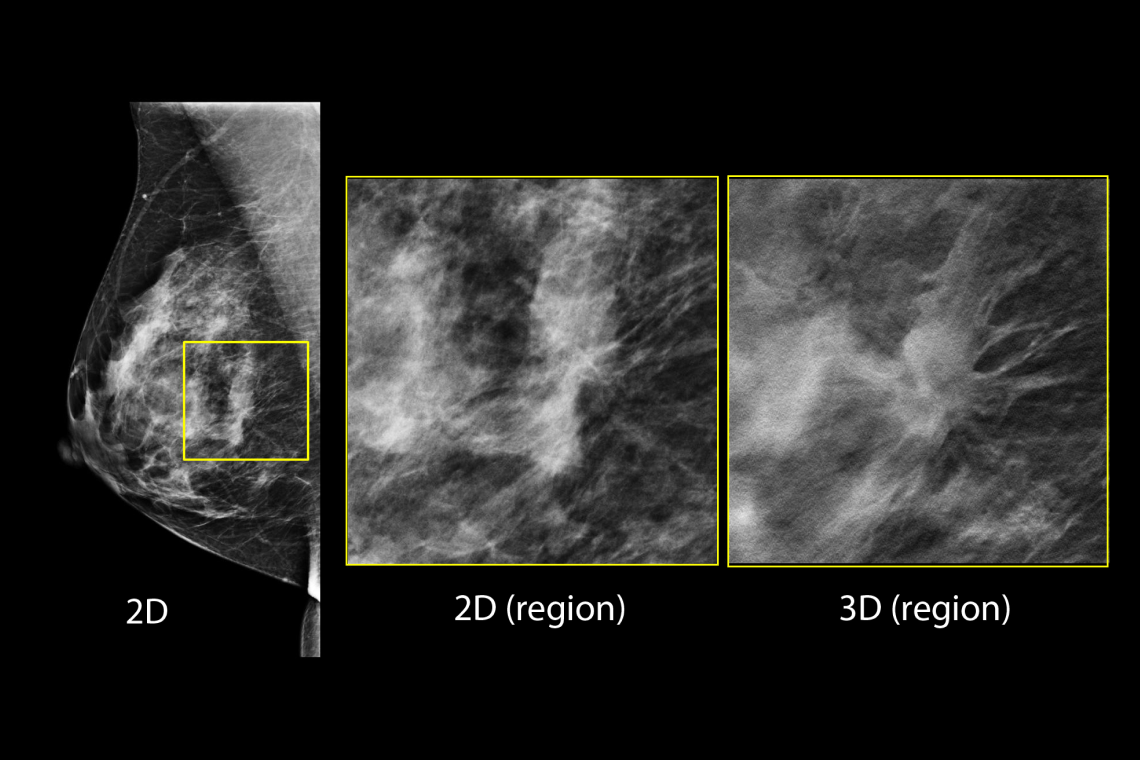

- Proven to detect 20%-65% more invasive breast cancers compared to 2D alone, an average increase of 41%.1

- FDA approved as superior for women with dense breasts compared to 2D alone.2,4

Hologic has further advanced breast cancer screening by producing 2D images from breast tomosynthesis data using C View software, resulting in a Low Dose Genius 3D Mammography exam with superior clinical performance compared with 2D alone.4

This Low Dose Genius 3D Mammography exam is performed in a rapid 3.7 second scan time for greater patient comfort and low patient dose, due to the elimination of 2D X ray exposures. The synthetic 2D images and 3D slices are reviewed together to make clinical decisions or diagnoses part of the Genius 3D Mammography screening exam.